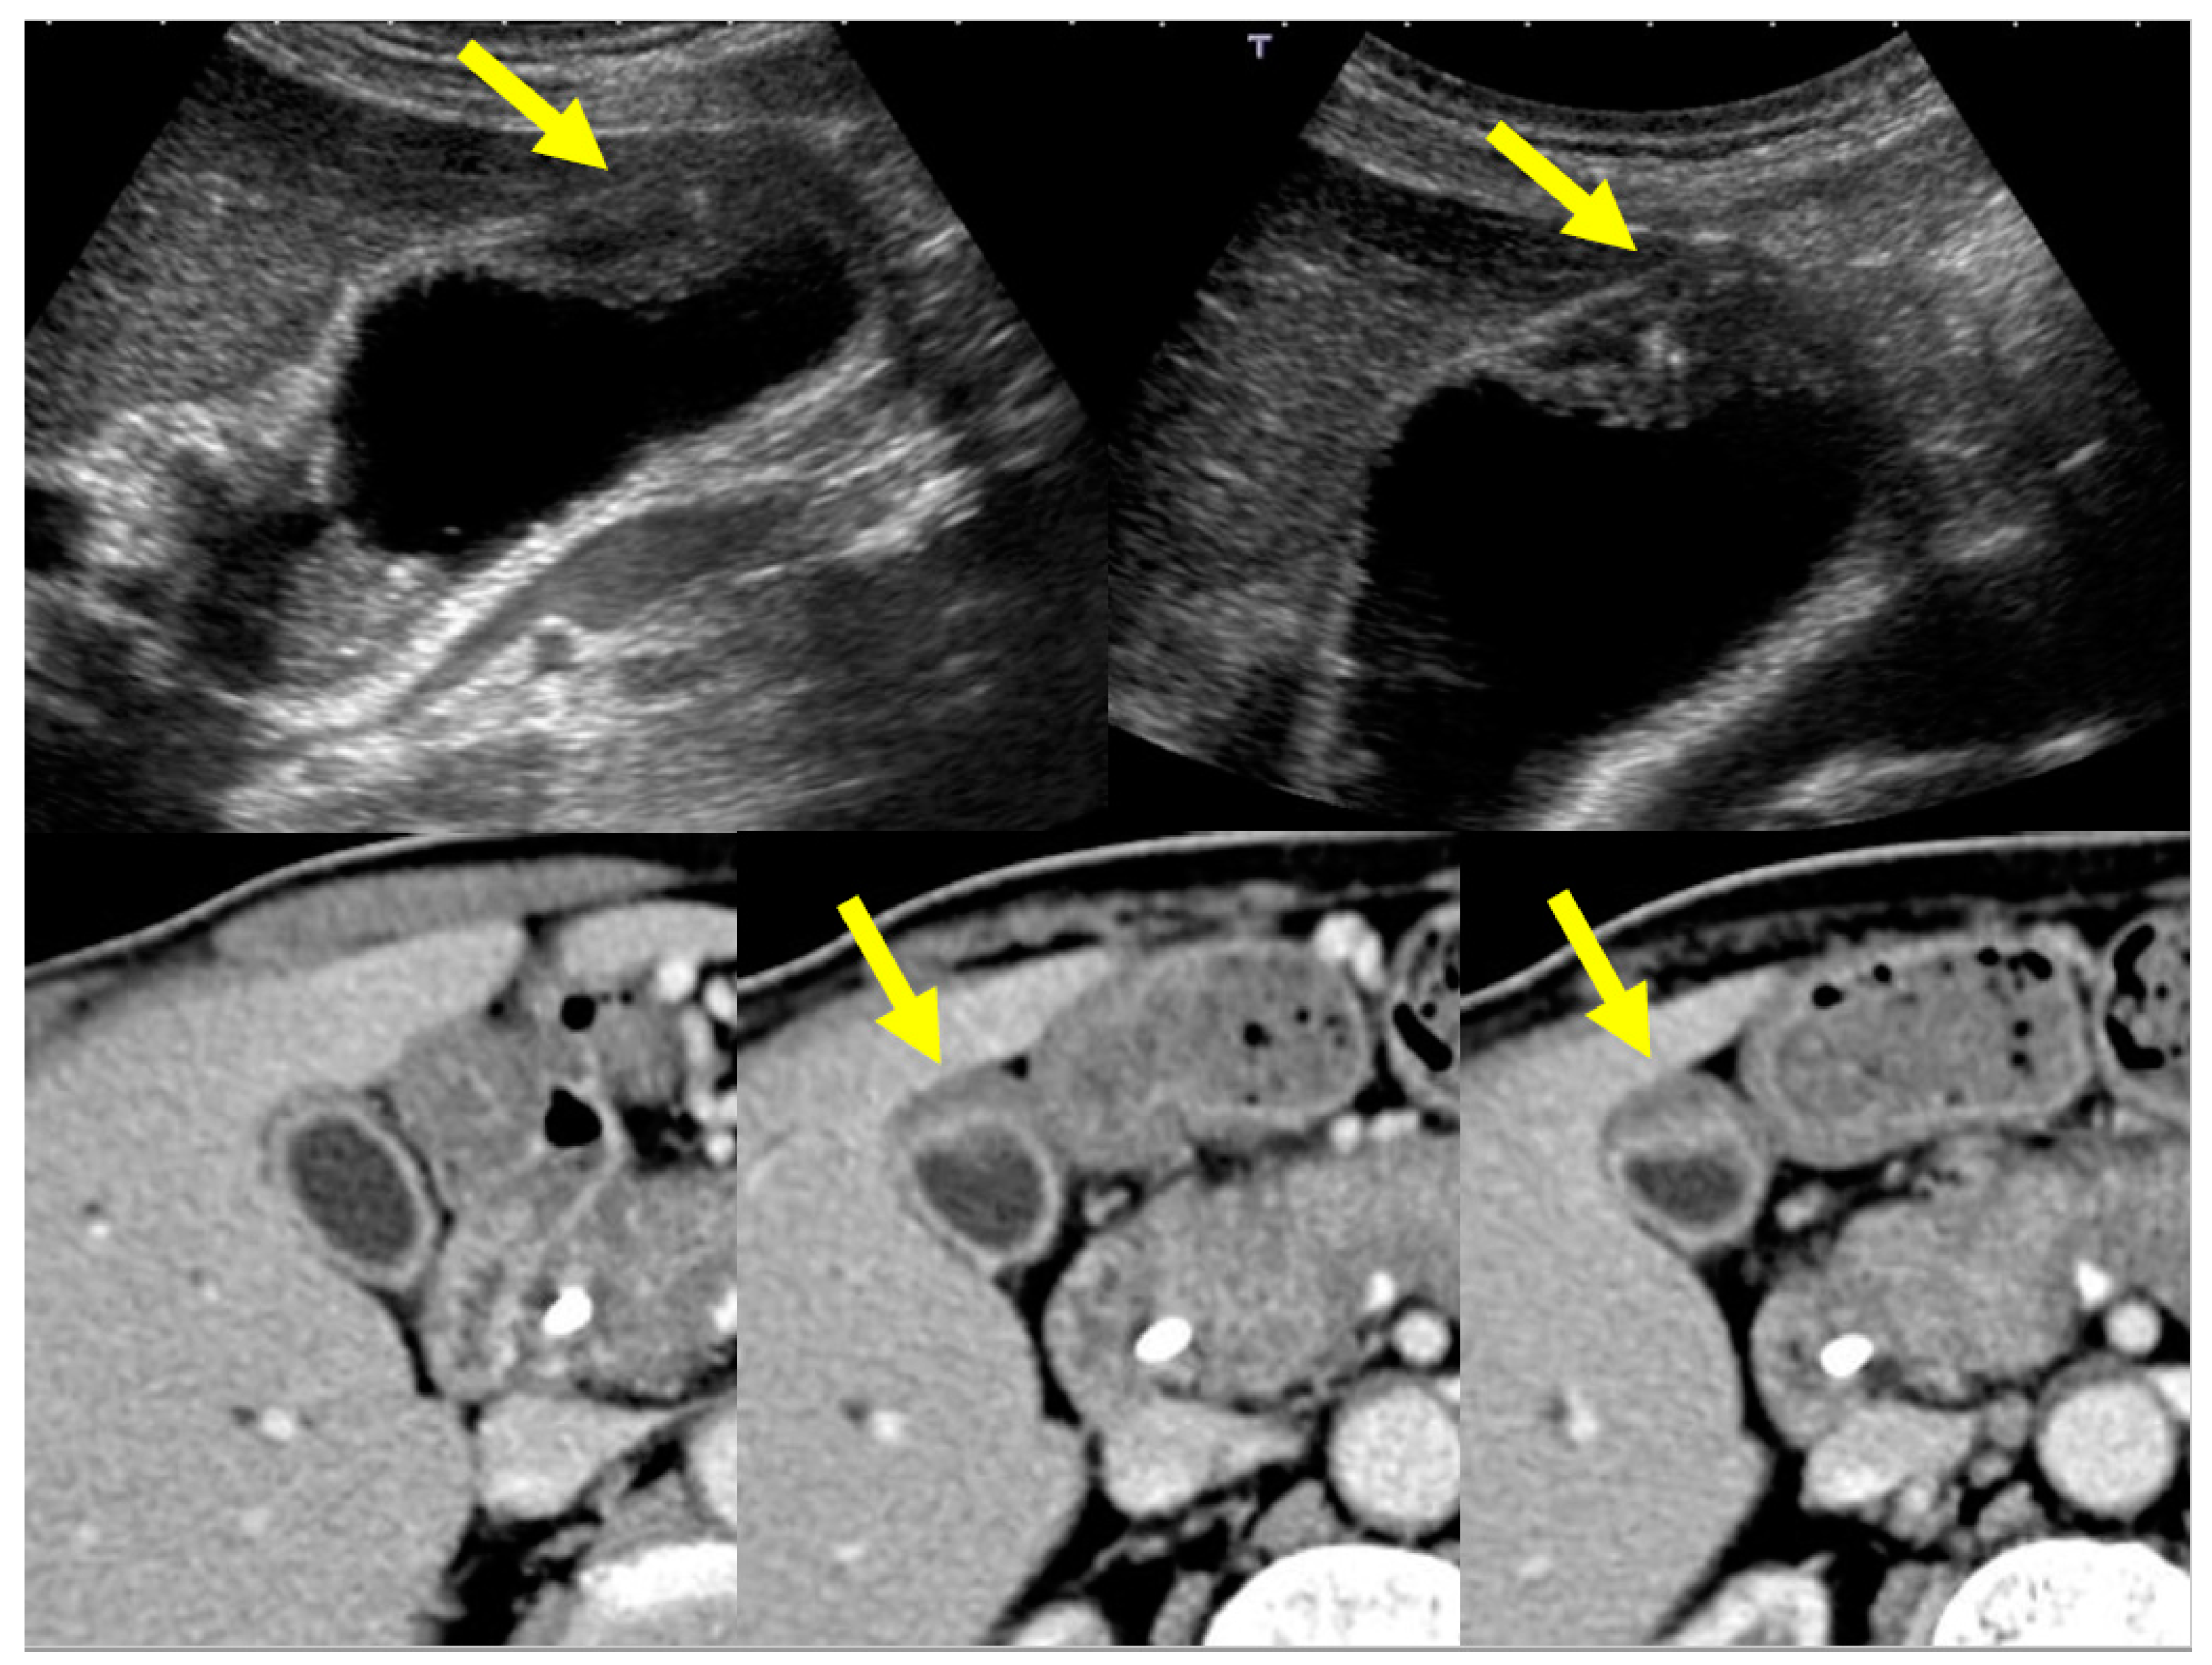

4.1. Diffuse Type of IgG4-CC

4.2. Localized Type of IgG4-CC